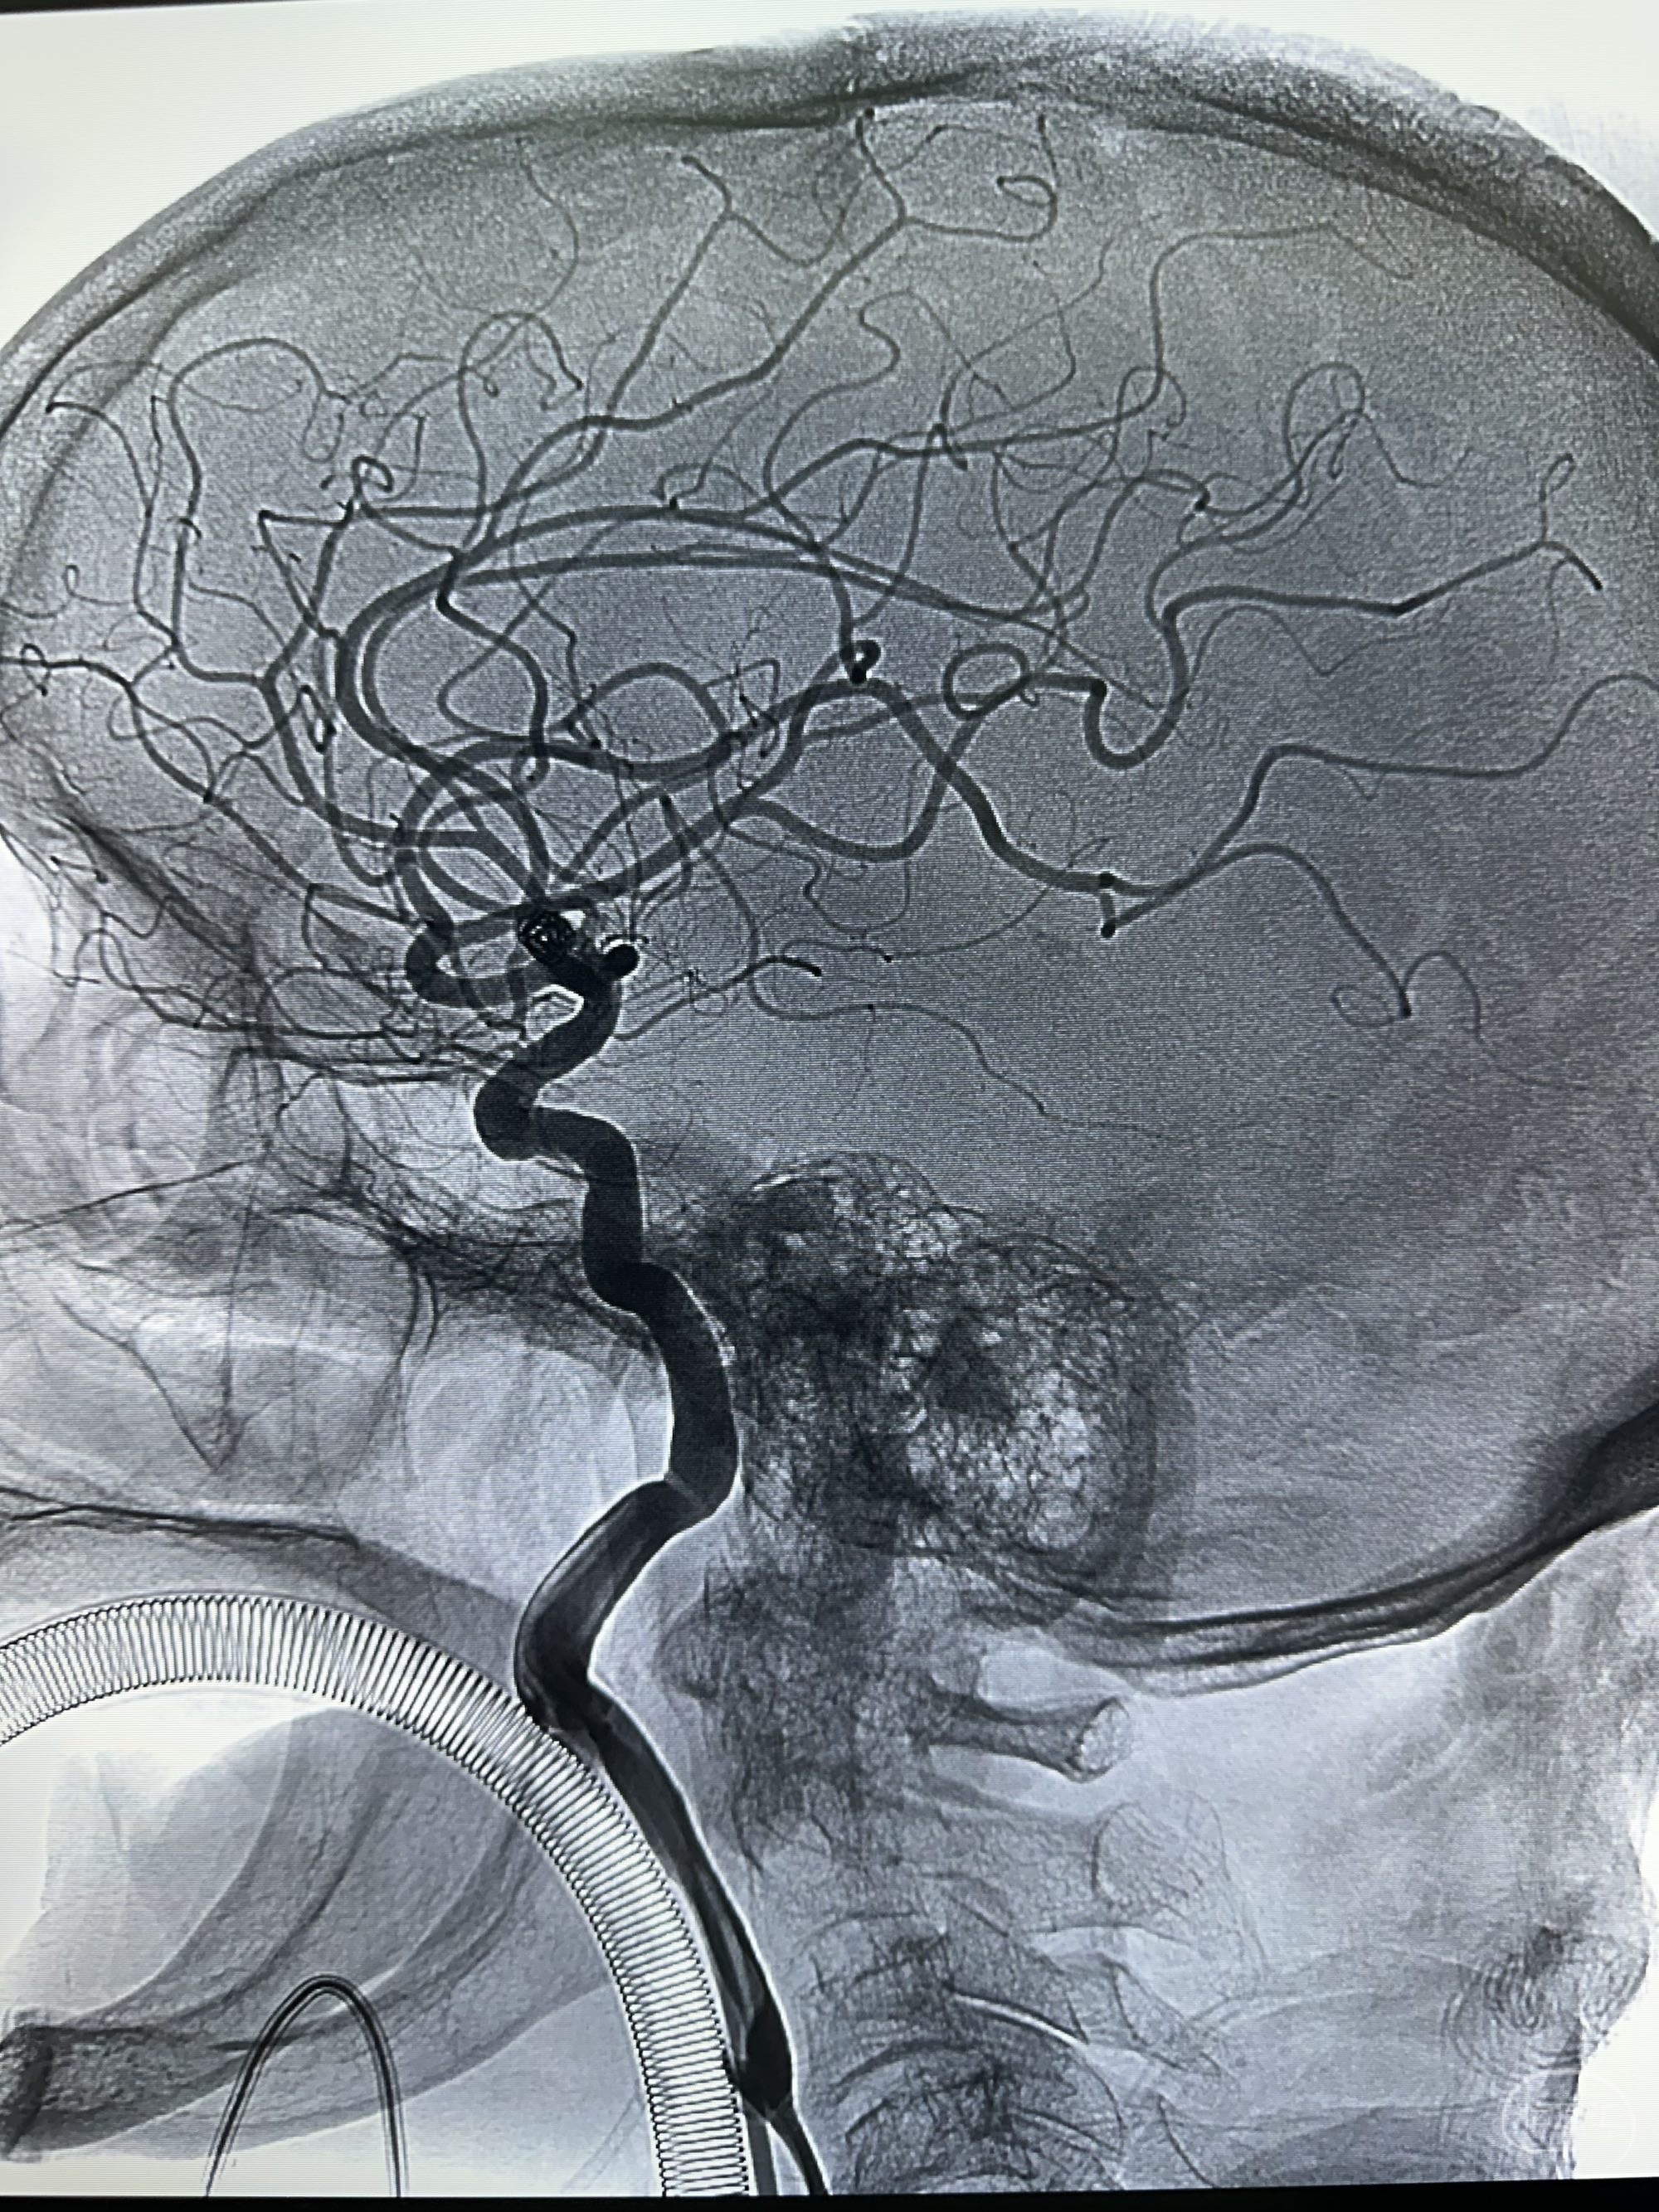

正位

侧位